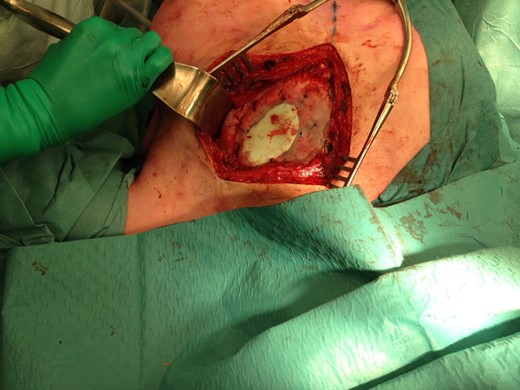

The size of the thoracic wall defect following resection measured 8 by 5.5 cm A patch was prepared using two polypropylene meshes and interpolate of methyl methacrylate (Fig. 3). The patch was placed and tightened to the periosteum using prolene sutures (Fig. 4). Figure 5 shows the resected tumour. Finally, subcutaneous tissue and skin were closed in layers using a Vicryl and intracutaneous Monocryl suture.

Positioning of the mesh and fixation to the periosteum of adjacent ribs.